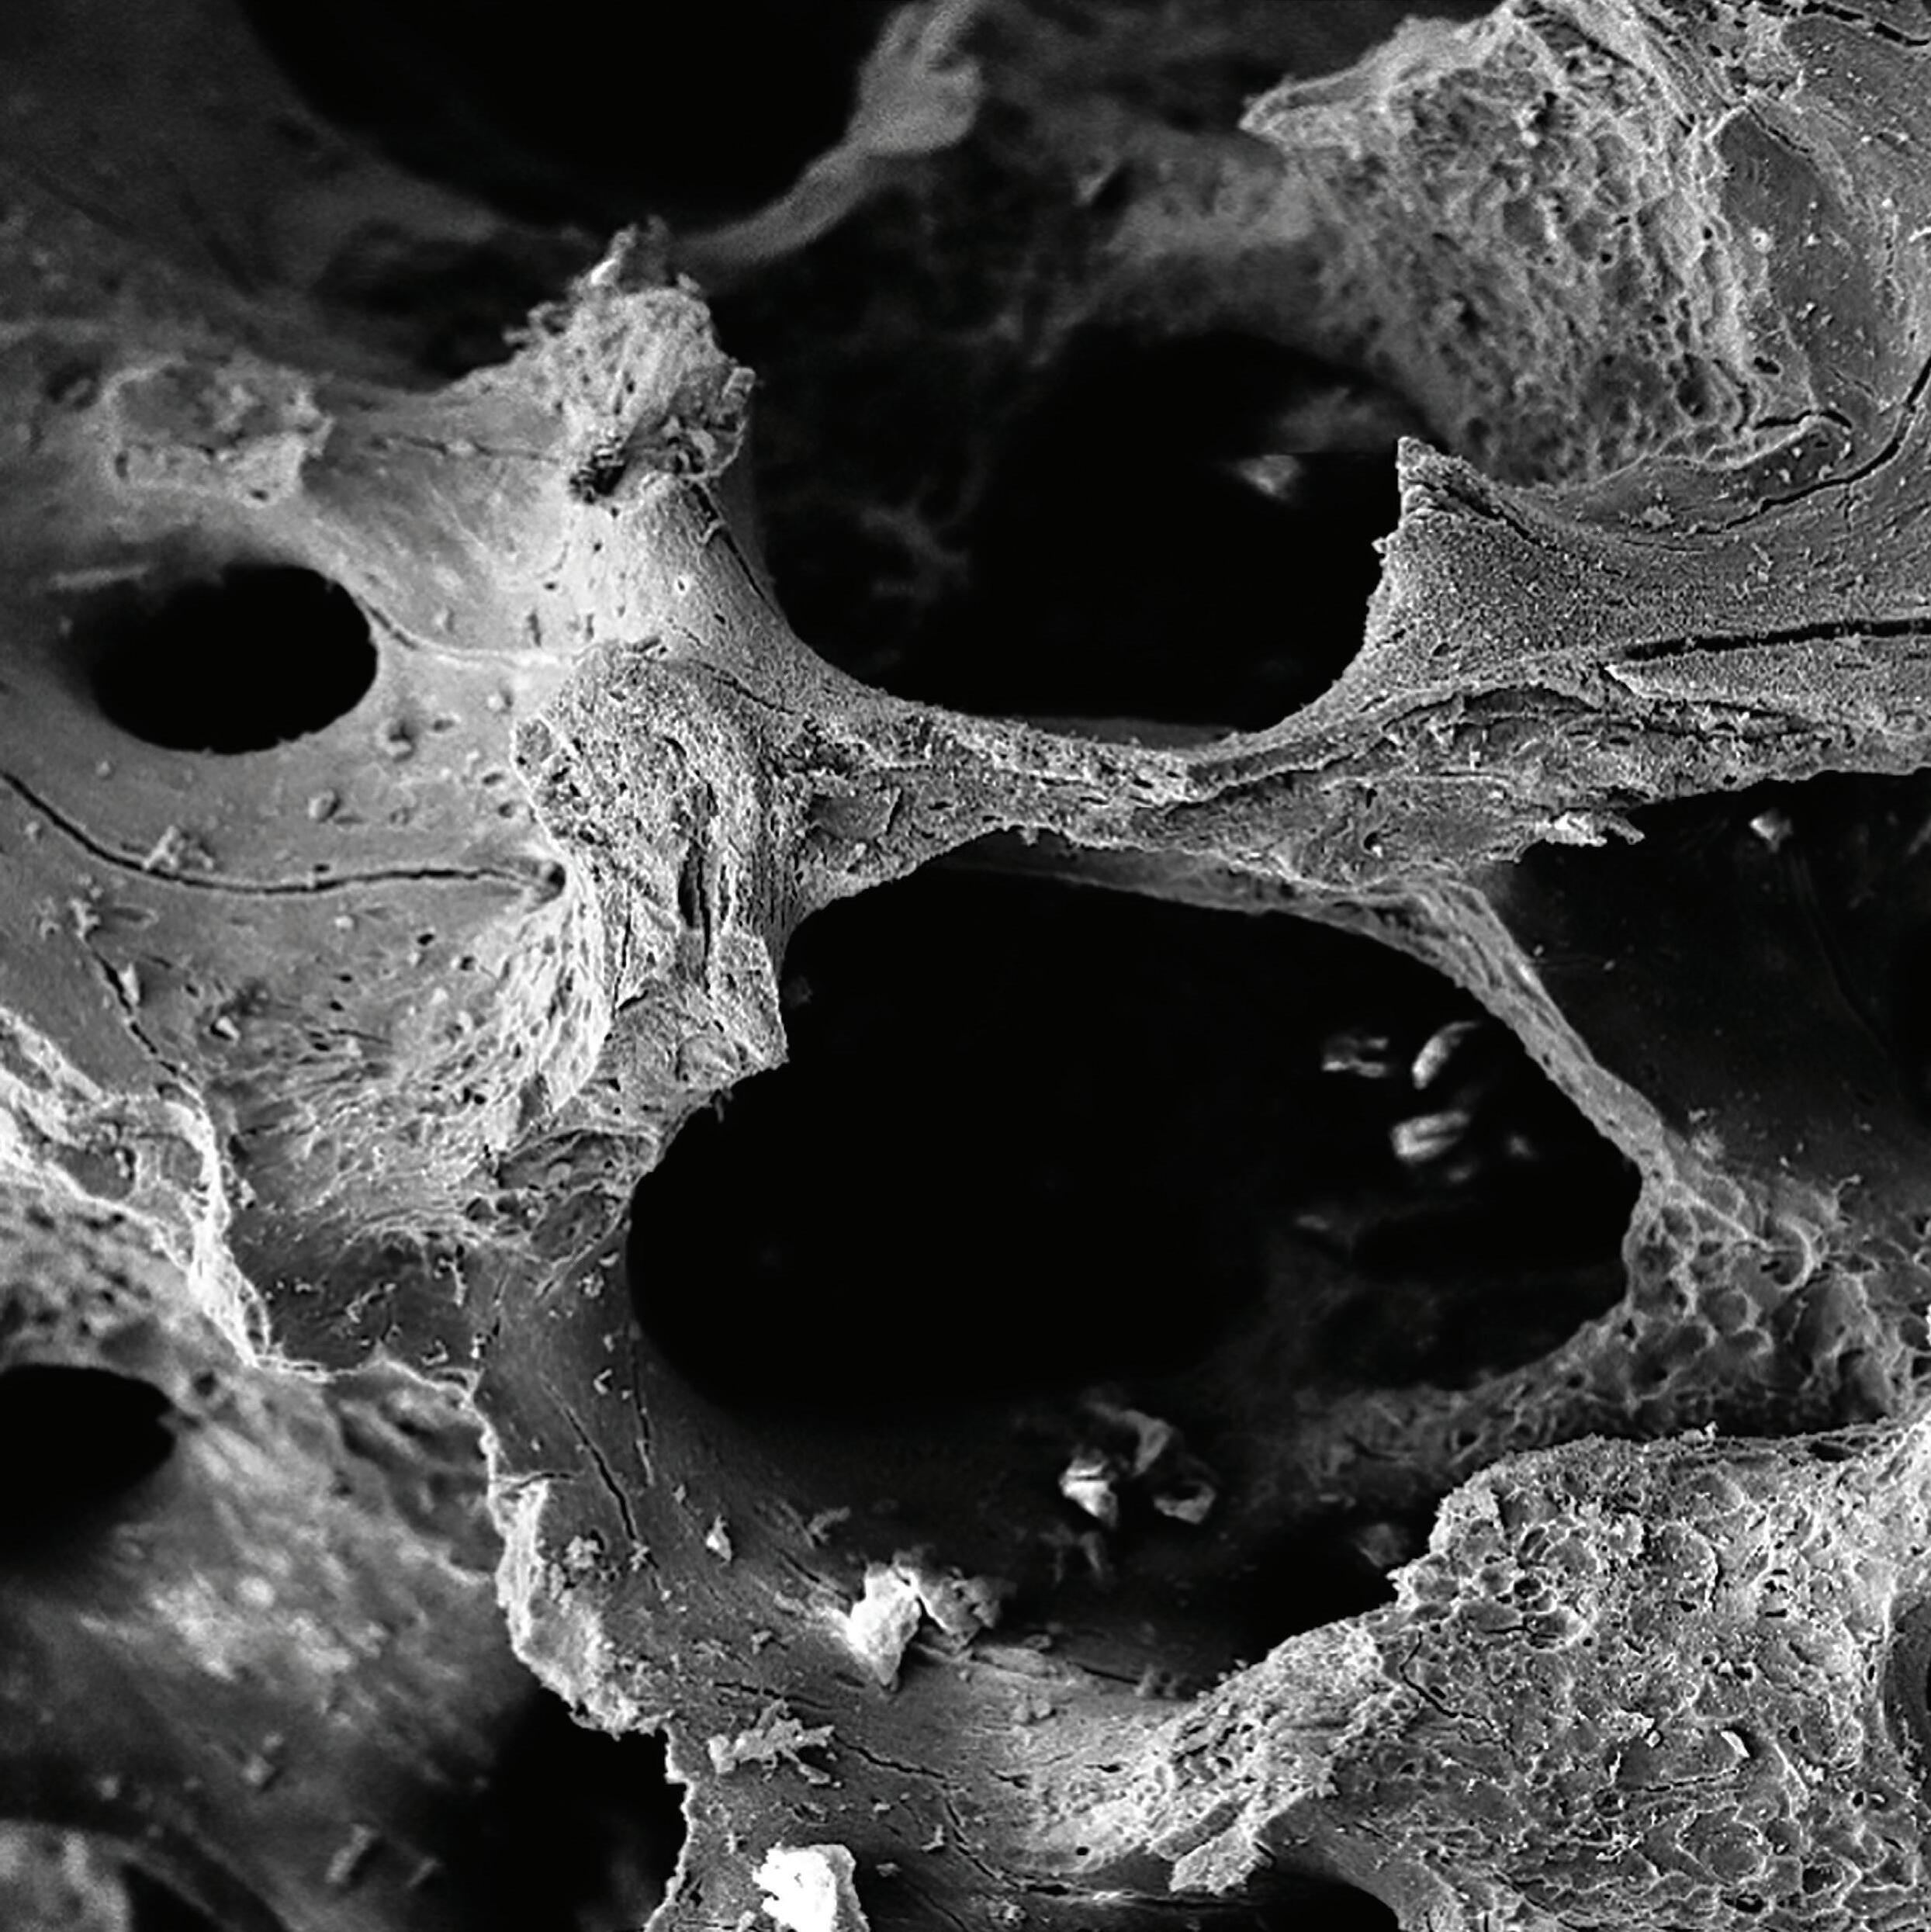

Xenograft, allograft and synthetic solutions, all engineered to offer greater range and treatment flexibility for virtually all requirements needed for the regeneration of hard and soft tissue deficits.

Striate+™ is the next generation of collagen membranes - expertly processed to remove all traces of DNA and immunogenic contaminants to create a favourable environment for the rapid regeneration of high-quality bone and soft tissue.

The allograft MinerOss® Blend offers a regenerative balance of approximately 70% cortical and 30% cancellous allograft chips, helping to form an osteoconductive scaffold for volume enhancement and effective site development to place dental implants.1

Continued advancements in regenerative medicine will support new ways to enhance tissue regeneration around implants, further improving long-term success and reducing complications.